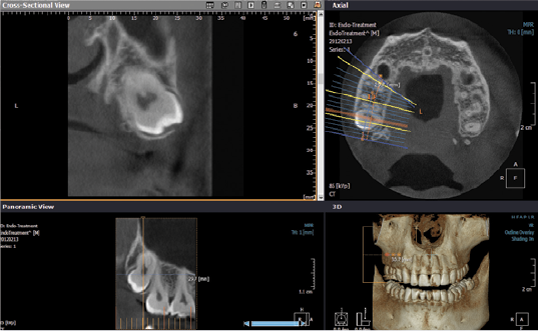

- Pianificazione terapeutica mediante trattamenti implantari

- Programmazione di chirurgia implatare guidata

- Follow up di trattamenti implantari